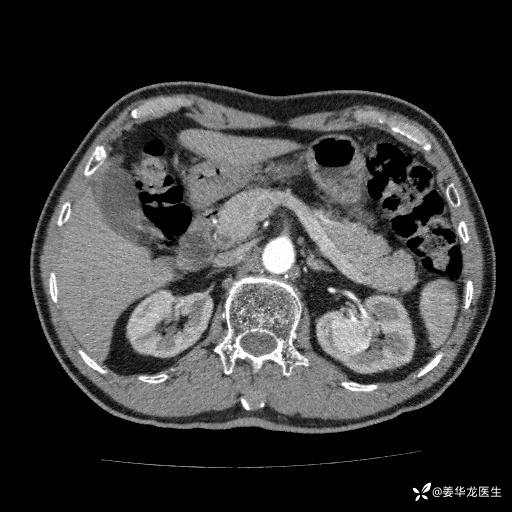

左肾中心型肾门部肿瘤39mm×34mm×36mm,右肾GFR25ml/min,部分切还是全切?

患者75岁老年男性,体重50kg,无高血压、肾病、糖尿病等基础病,检查发现左肾中心型肾门部肿瘤,右肾GFR只有25ml,无肉眼血尿,无镜下血尿。入院验血常规检查均正常,包括肾功能,肌酐102.7umol/L.

二、左肾肿瘤与左肾集合系、左肾动静脉关系密切,左肾部分切除术可行吗?成功率有多大?成功部分切后,肾功能还有多少?

三、患者无任何基础病,为什么右肾GFR只有25ml/min,反尔有肿瘤的左肾GFR达38.8ml/min?